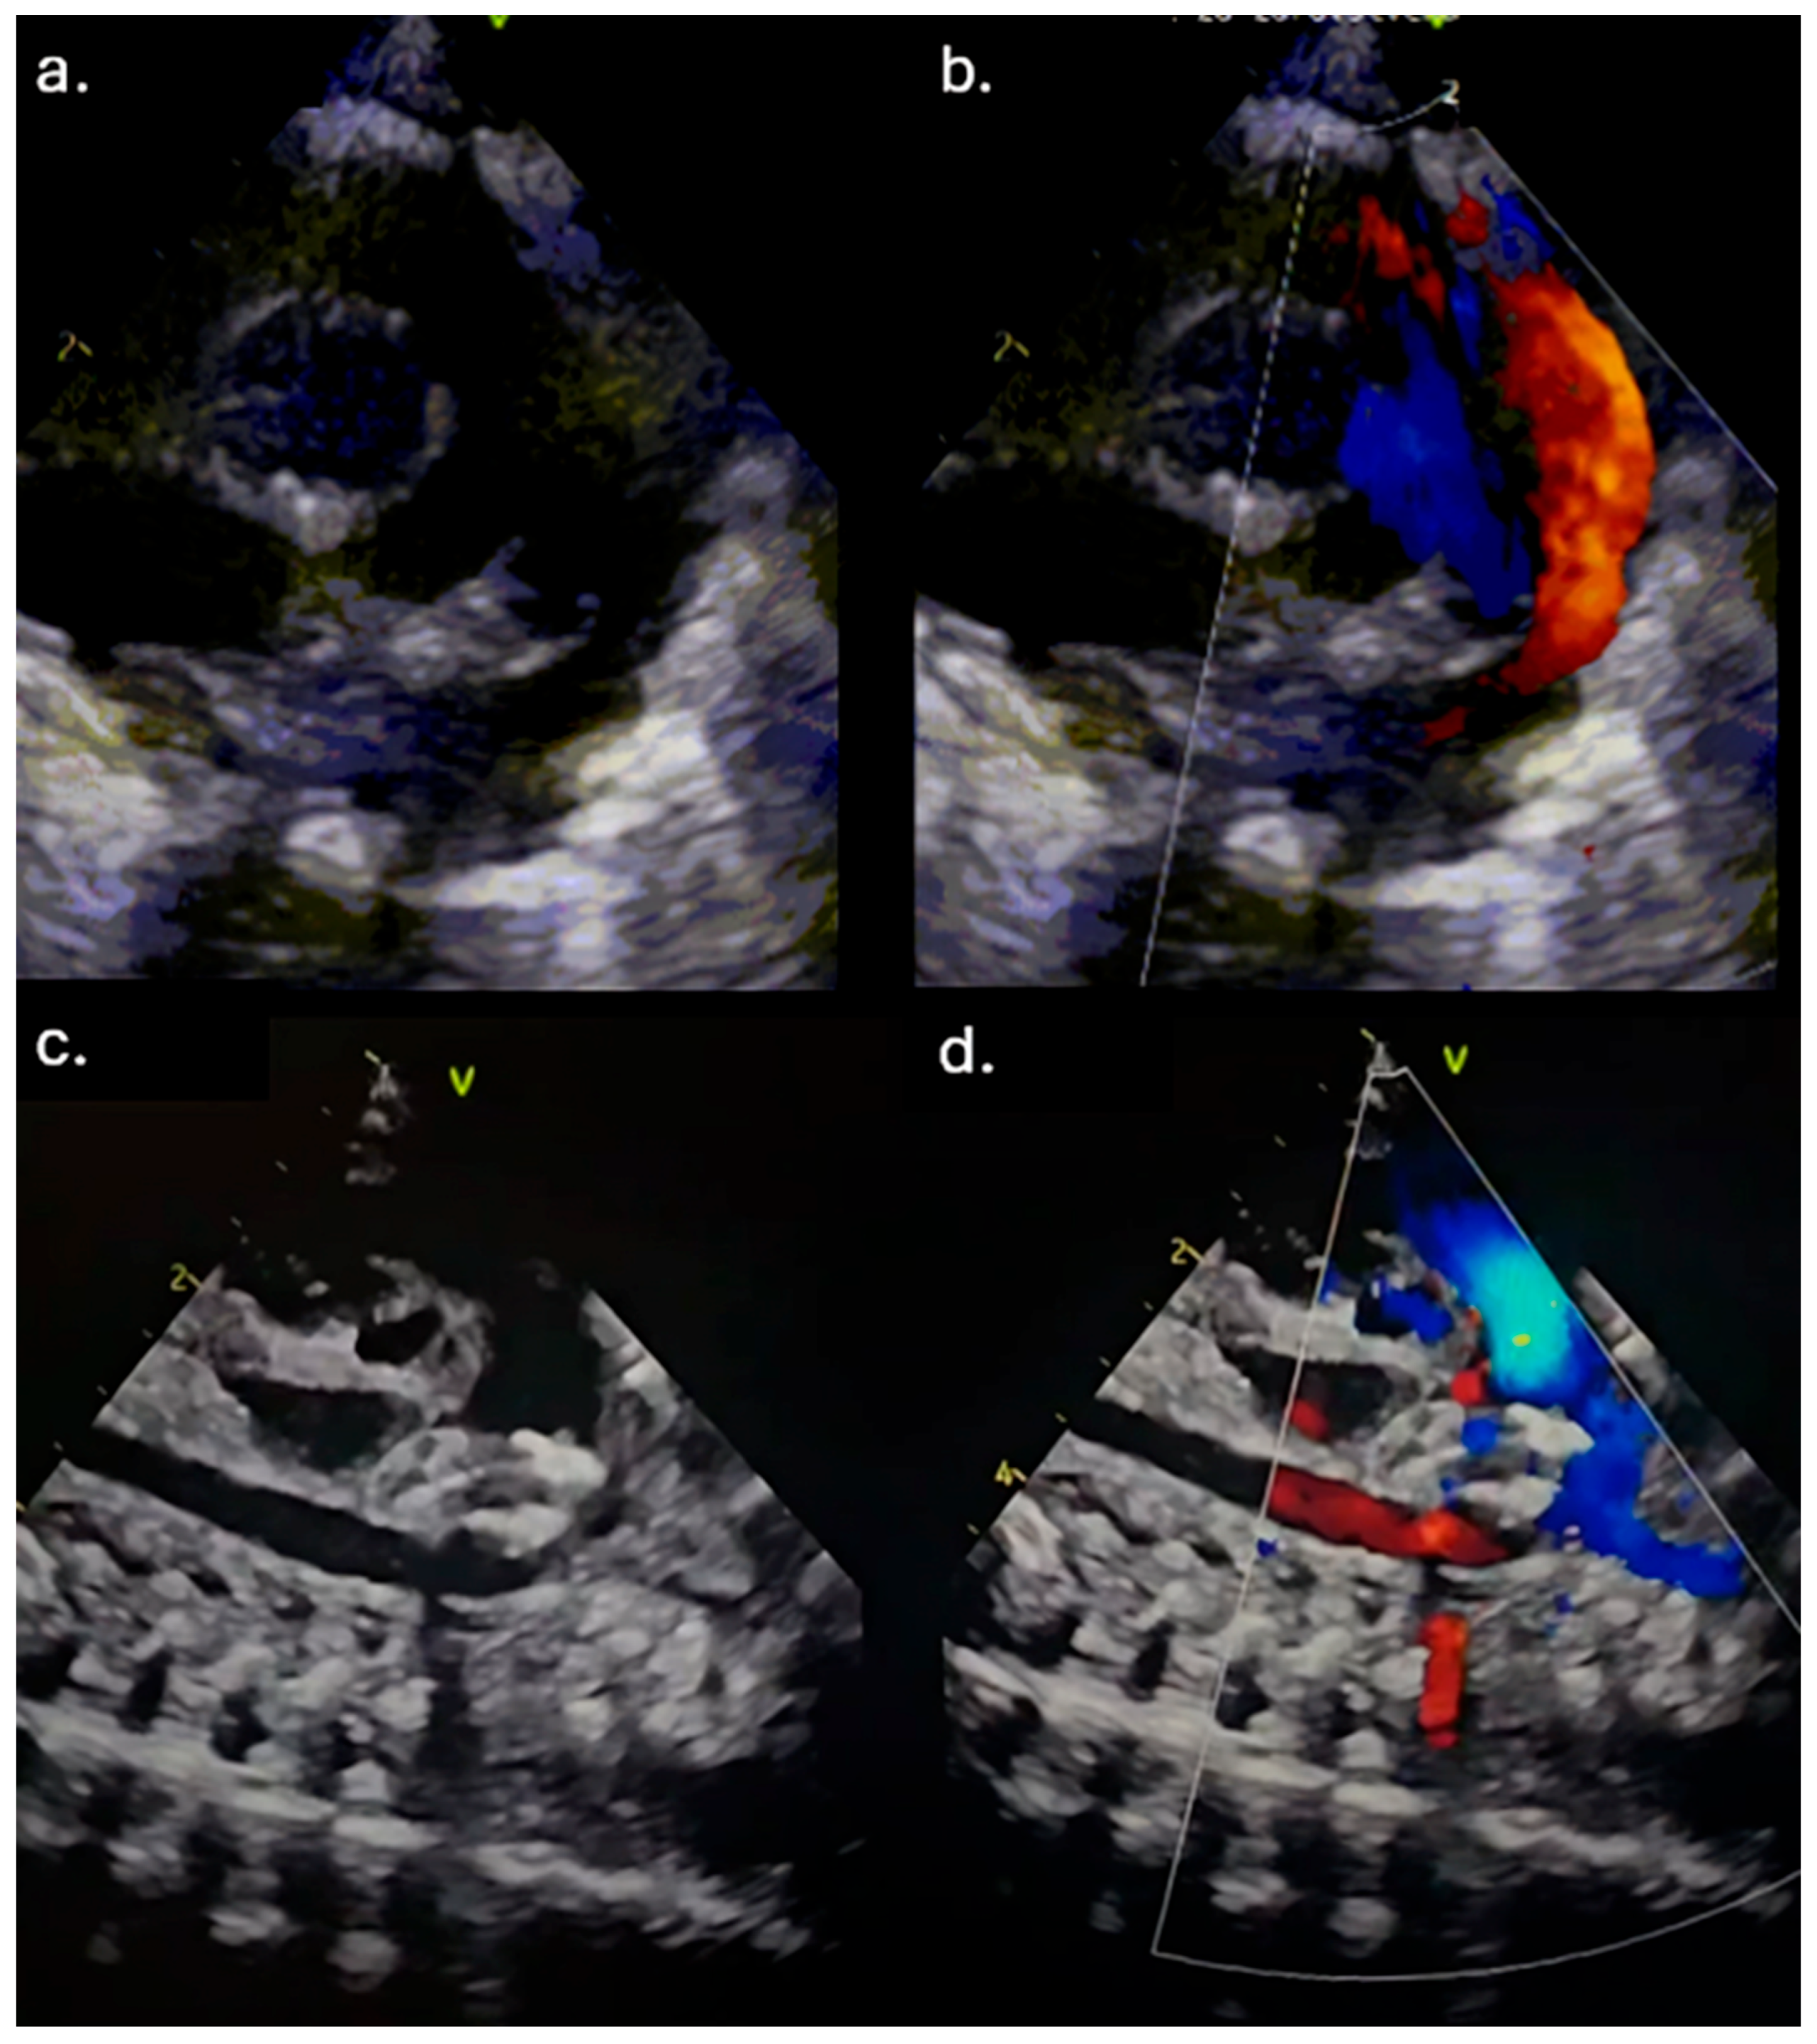

The first patient was weaned from mechanical ventilation three days after the procedure. A control echocardiography examination revealed a decreased left ventricular EDD and LA/Ao ratio. Three weeks after the procedure, the patient was discharged with a body weight of 2300 g. The second patient was extubated 2 weeks after the procedure, and even an X-ray of the severe BPD displayed an improved condition (Figure 3). An echocardiography examination pointed out a decreased left ventricular EDD with mild pulmonary artery hypertension. Consequently, sildenafil was initiated. After 6 weeks, the patient was transferred to the regional hospital due to low body weight (1880 g). In the third case, the patient was placed on conventional mechanical ventilation immediately after the intervention, and the inotropes were discontinued after two days. Renal function was normalized. She weaned from mechanical ventilation after 3 weeks.

Figure 3. X-ray findings before (A) and after (B) transcatheter PDA closure.